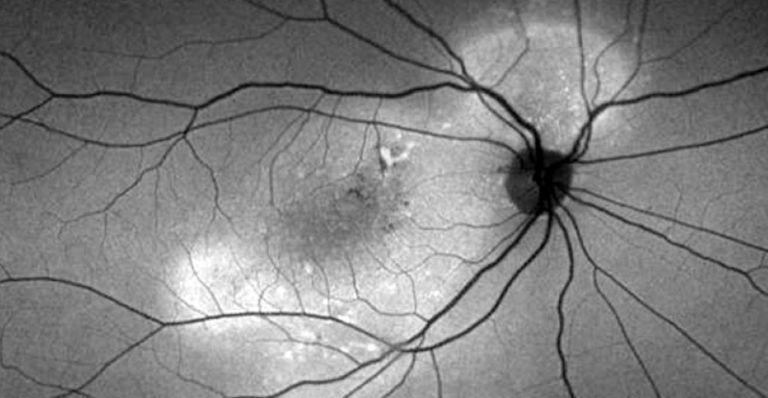

Lesiones viteliformes: Enfermedades como la de Best o la distrofia viteliforme del adulto. Lo que se ve en la tomografía no es fluido, sino material de desecho de fotorreceptores. La clave es la autofluorescencia, donde estas lesiones brillan de forma característica.